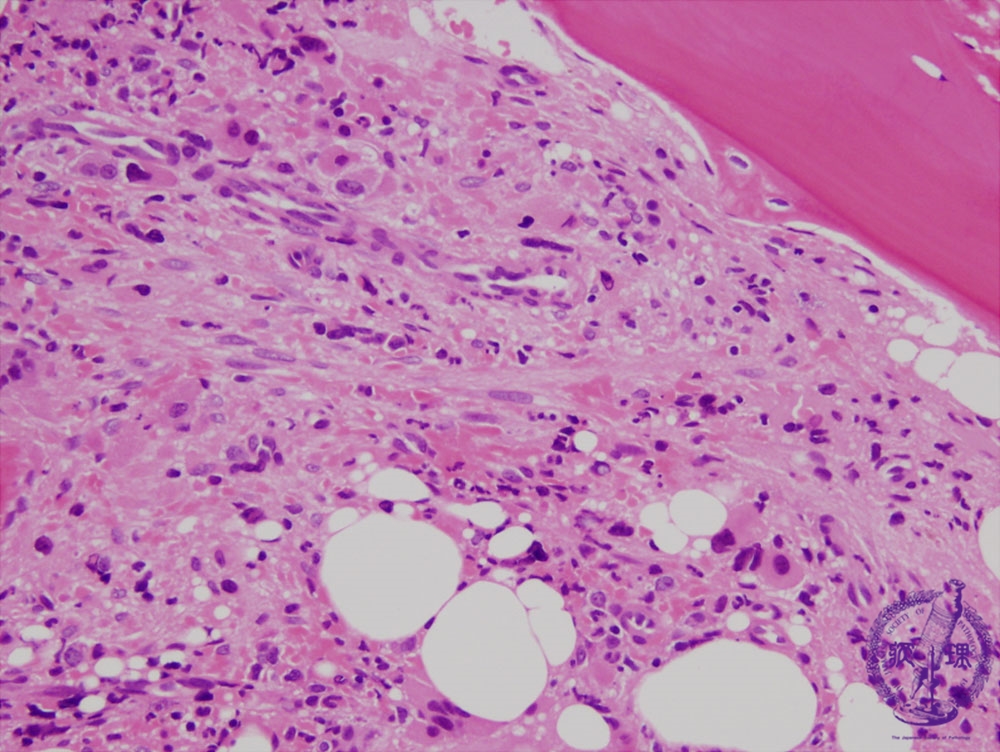

- 1.Bone marrow / Hematopoietic system

- (6) Myeloproliferative disorders (Polycythemia vera)

Microscopic image (H&E high power view): Fibroblasts are also proliferating in the hypercellular marrow. As with fibroblasts proliferation, marked deformity is observed in hematopoietic cells. Megakaryocytes are numerous. The pale pink fibrous tissue is found in the background.